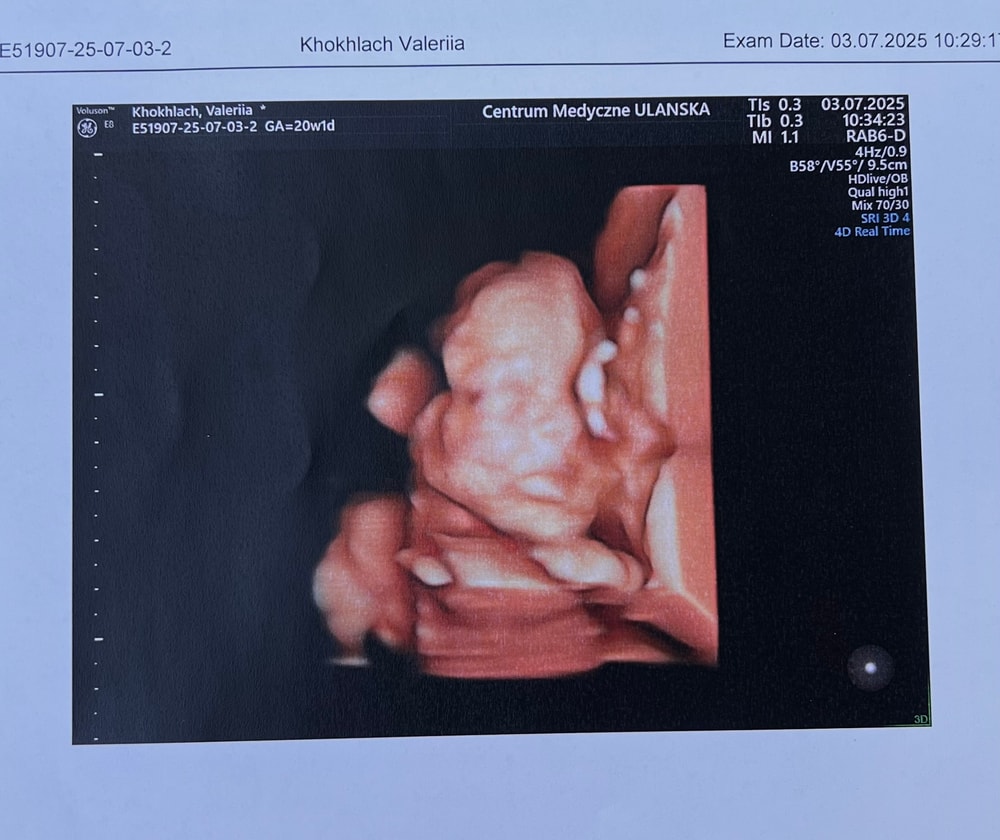

Прошли второй скрининг!)

Анализы, скринингиПару дней назад была на втором скрининге, по узи все отлично! Развивается хорошо (тьфу тьфу тьфу)

Какой уже большой человечек💜

Марья, Сама в шоке, только недавно такой фасолиной маленькой была, щас уже 25 см от макушки до пяточек